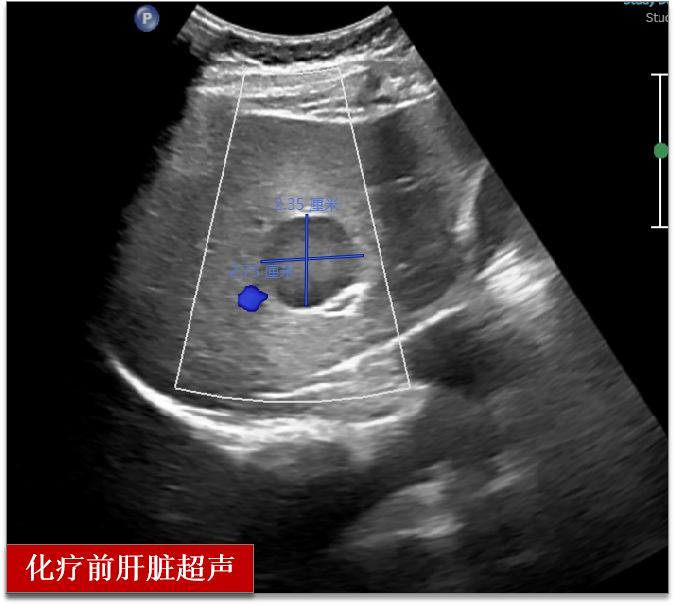

检查后发现肝部多发占位

经过穿刺后病理确诊乳腺癌伴肝脏转移

两个周期的化疗后

超声检查提示肝脏肿瘤完全消失